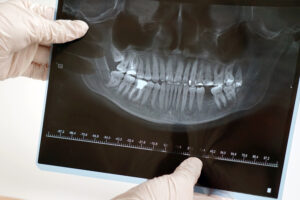

歯科治療の精度向上と効率化は、近年、技術革新によって大きな進展を遂げています。歯科用CTスキャン(デンタルCT)は、その革新的な技術の一つとして、従来の診断手法を補完し、さらには置き換えつつあります。これにより、歯科医師は患者の口腔内の詳細な情報を手に入れ、より精密な診断を行うことが可能になりました。また、患者にとっても、より安全で効率的な治療が提供されるようになっています。ここでは、歯科用CTスキャンの利点を、より詳細に解説します。

従来のX線診断では2Dの平面的な画像しか得られませんが、歯科用CTスキャンは、3Dの立体的な画像を提供します。これにより、歯科医師は歯や顎、骨構造、神経、血管など、口腔内のあらゆる部分を詳細に把握することができます。3D画像を用いることで、単純な2D画像では見逃しがちな微細な異常や問題も明確に確認でき、治療計画をより精密に立てることができます。

例えば、インプラント治療の計画においては、骨の密度や形状、顎の骨の厚さなどが重要な要素となります。歯科用CTスキャンでは、これらを正確に把握することができ、インプラントの最適な埋入位置や角度を決定する際に非常に有用です。従来のX線ではわからない骨の厚みや角度、神経の位置などを詳しく確認できるため、インプラント治療の精度が飛躍的に向上します。